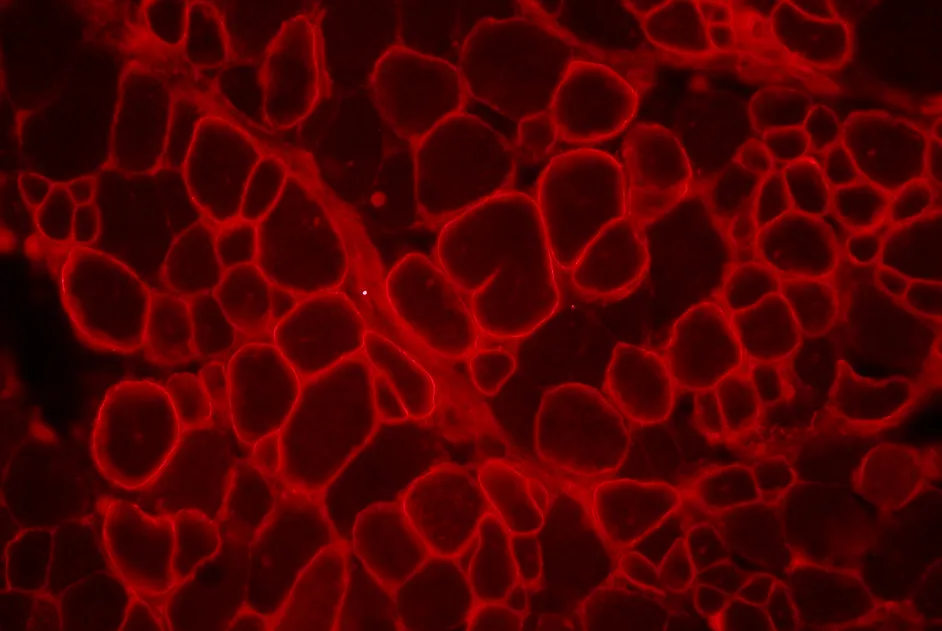

Effets bénéfiques du tadalafil sur le débit sanguin musculaire d'effort d’hommes atteints de myopathie de Becker, âgés de 18 à 55 ans, ambulants, sans problème cardiaque

Rétablir la fonction de la dysferline mutée en la relocalisant à la membrane à l’aide de peptides dérivés de la dysferline.